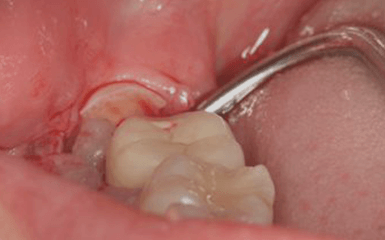

微創無痛拔牙,即局部麻醉後,應用微動力技術、微創拔牙器械,輕輕插入需要拔除的病牙,使牙齒鬆動脫離。這種方法對周圍組織損失極小,不會損傷臨近牙齒,且創口小、時間短、併發症少,可以幫助患者更為加速癒合,也大大減少了患者對拔牙的心理恐懼感。

拔除

微創拔除病牙,根據牙齒的複雜程度需要的時間也不同。